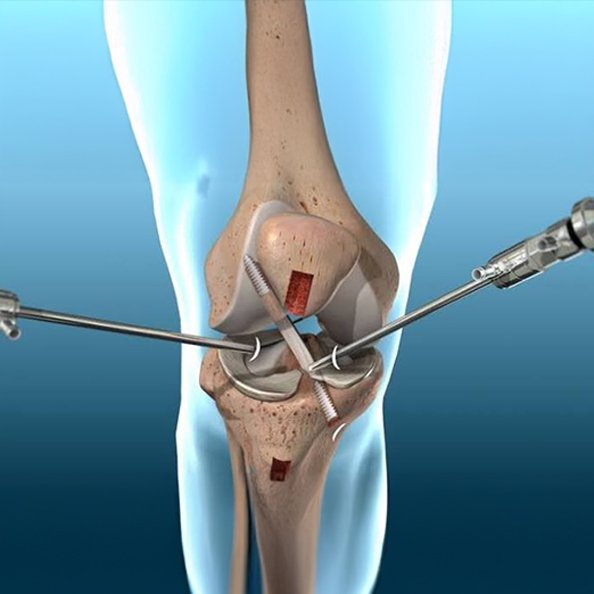

Knee Arthroscopy Surgery

Minimally invasive knee arthroscopy surgery for injuries and Ligament Tear ( ACL, PCL, MCL, LCL), Meniscus Tear, Cartilage Loss ensuring precision treatment, faster recovery, and improved joint function.